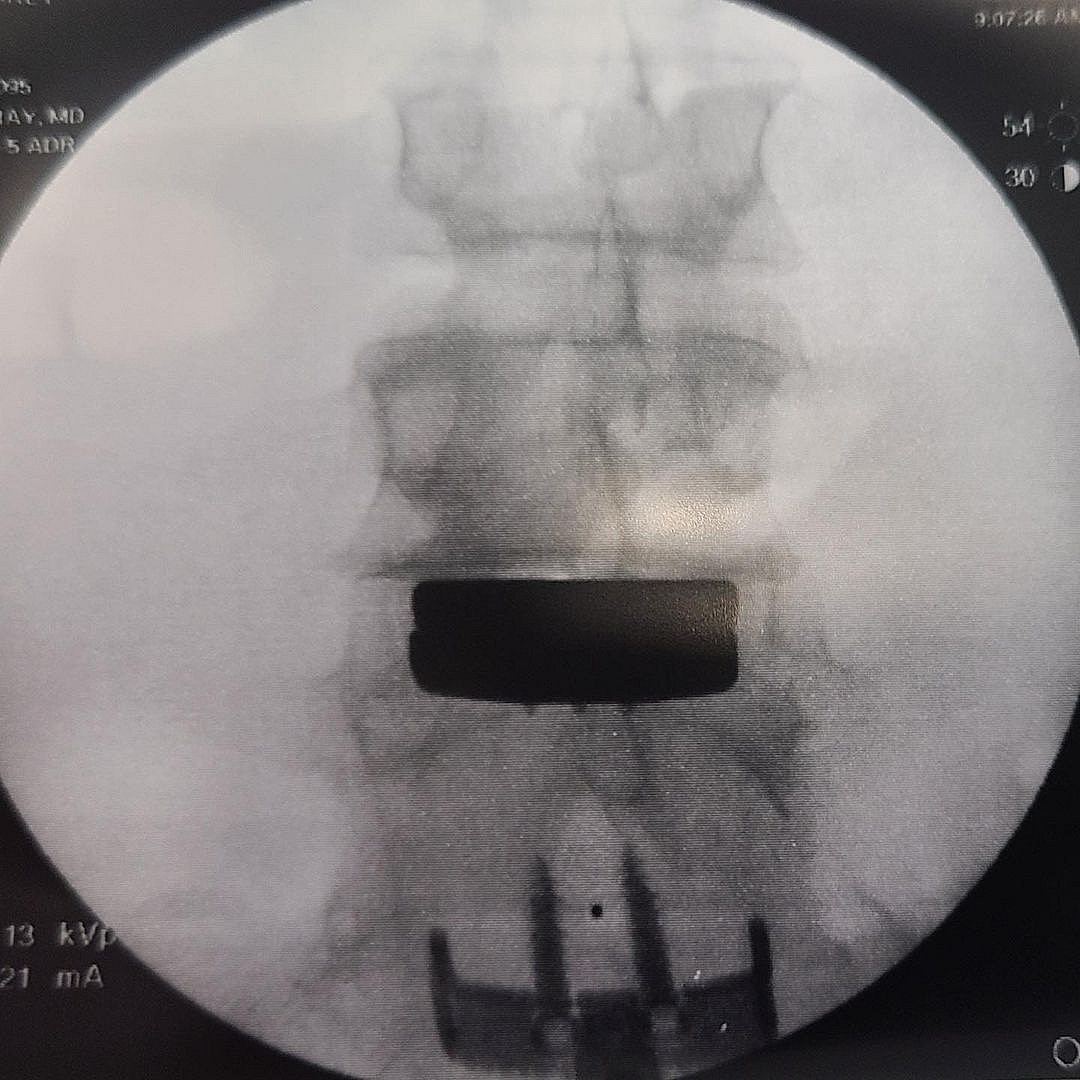

Check Out X-Rays Of The Finished Job!

Motocross legend Carey Hart was hospitalized after receiving a “lower spine disc replacement” and the famous rider decided to share images from inside the surgery!

“One down and one to go!!!!! Lower spine disc replacement was a success!!! up and out of bed and walking, just a few hours post-surgery. Been up 5 times since this. Special thank you to Dr. Bray who performed the surgery, and Layla who truly makes this all happen. The staff here is nothing short of amazing. I am very lucky to have this team to bolt me back together,” Hart captioned the footage.

Hart has previously opened up about the horrible back pain he has endured due to fracturing it in the past. In 2014, Carey described the situation to Rolling Stone, saying, “I had my spine fused nine weeks ago, the doctor thinks I compression-fractured my lower spine at least 10 to 12 times, so we had to go in and take care of it.”